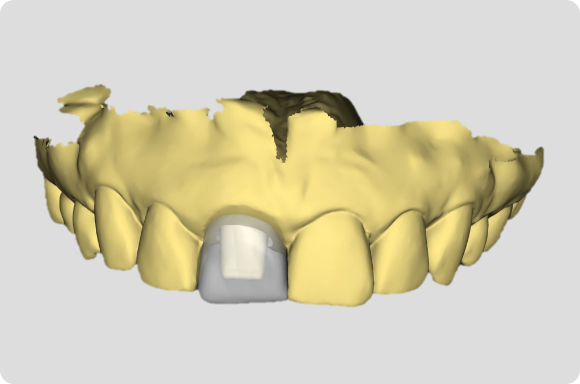

En utilisant un enseignement basé sur les procédures1, ce niveau aidera le clinicien à évoluer vers des concepts chirurgicaux et prothétiques plus avancés grâce au traitement de cas d’implants antérieurs à dent unique.

Tout au long de ce niveau, les cas couvrent des sujets tels que : Évaluation de l’os buccal et apical pour une implantation immédiate, Greffe autour d’implants immédiats (technique de la double zone), Définir l’orientation de l’implant – Les règles de six, Évaluer la stabilité primaire pour une mise en charge immédiate, Options et conceptions de piliers CAO/FAO. À la fin de ce niveau, les participants comprendront comment placer et restaurer un implant à dent unique dans la zone antérieure. Les participants sont invités à poursuivre leur formation au niveau 4, qui se concentrera sur les cas d’implants multiples.